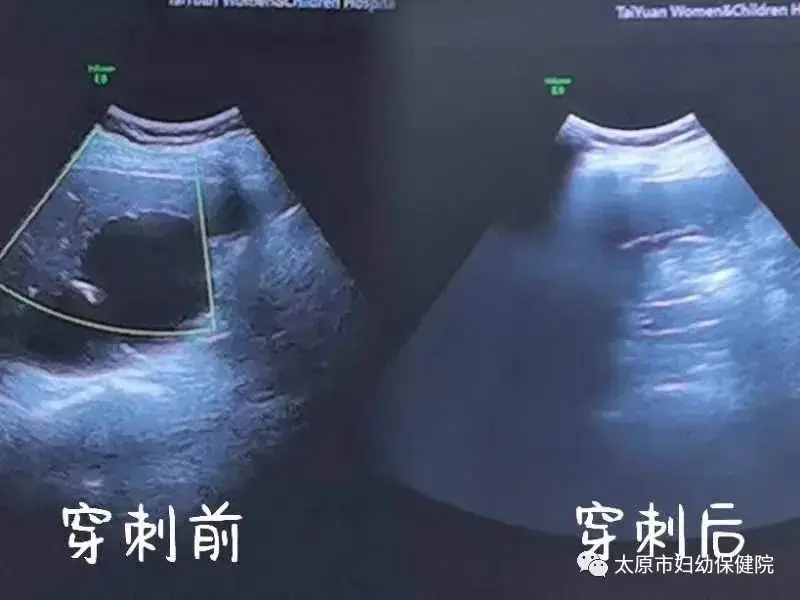

3. 引流方式: 囊肿引流方法包括穿刺引流、外科手术引流等多种方式。穿刺引流一般引流出的时间较短,可在几小时内完成;而外科手术引流则通常需要更长的时间,有时需要留置引流管几天才能全部引流出来。